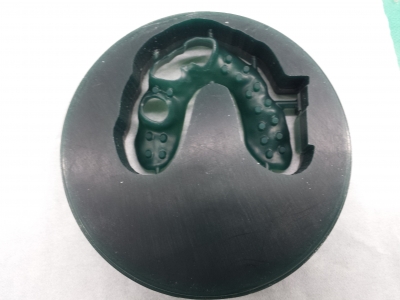

フォローアップセミナーでは、アソアライナー導入に向けて

歯科技工士の観点からお話をさせていただきました。